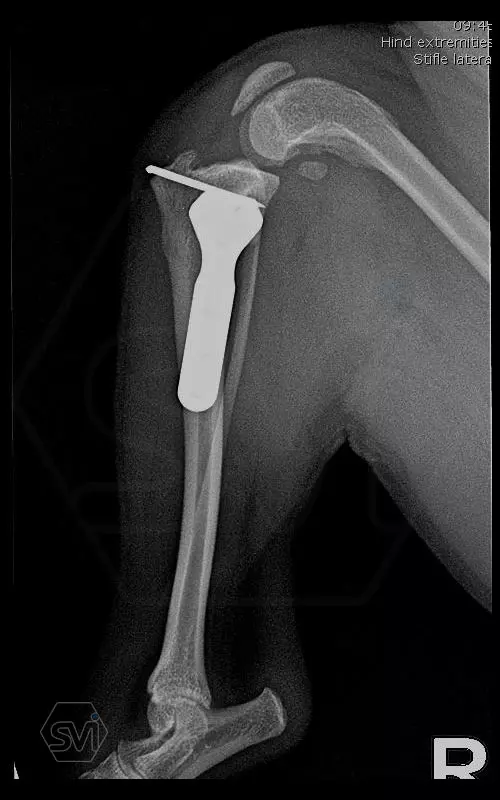

Introducing the TPLO-M „terraced” plate family from Smartvetimplants.com

In small dogs, medial patella luxation (MPL) and the rupture of anterior cruciate ligament (RACL) often occur simultaneously. During the surgical procedure, the joint must be stabilized and the patella fixed in the middle axis at the same time.

The solution of Smatvetimplants is the TPLO-M plate family with terrace:

Between October 2020 and December 2021, we performed 19 TPLO-M surgeries at the Animal Hospital in Nyíregyháza,: 16 times used the mini (2.0 R12) and 3 times the small (2,4 R15) TPLO-M plate.

The experience is very encouraging, we find the system and plates suitable for the simultaneous treatment of MPL and RACL. ( in case of 4/4 pat. lux. also). We will back soon with details.